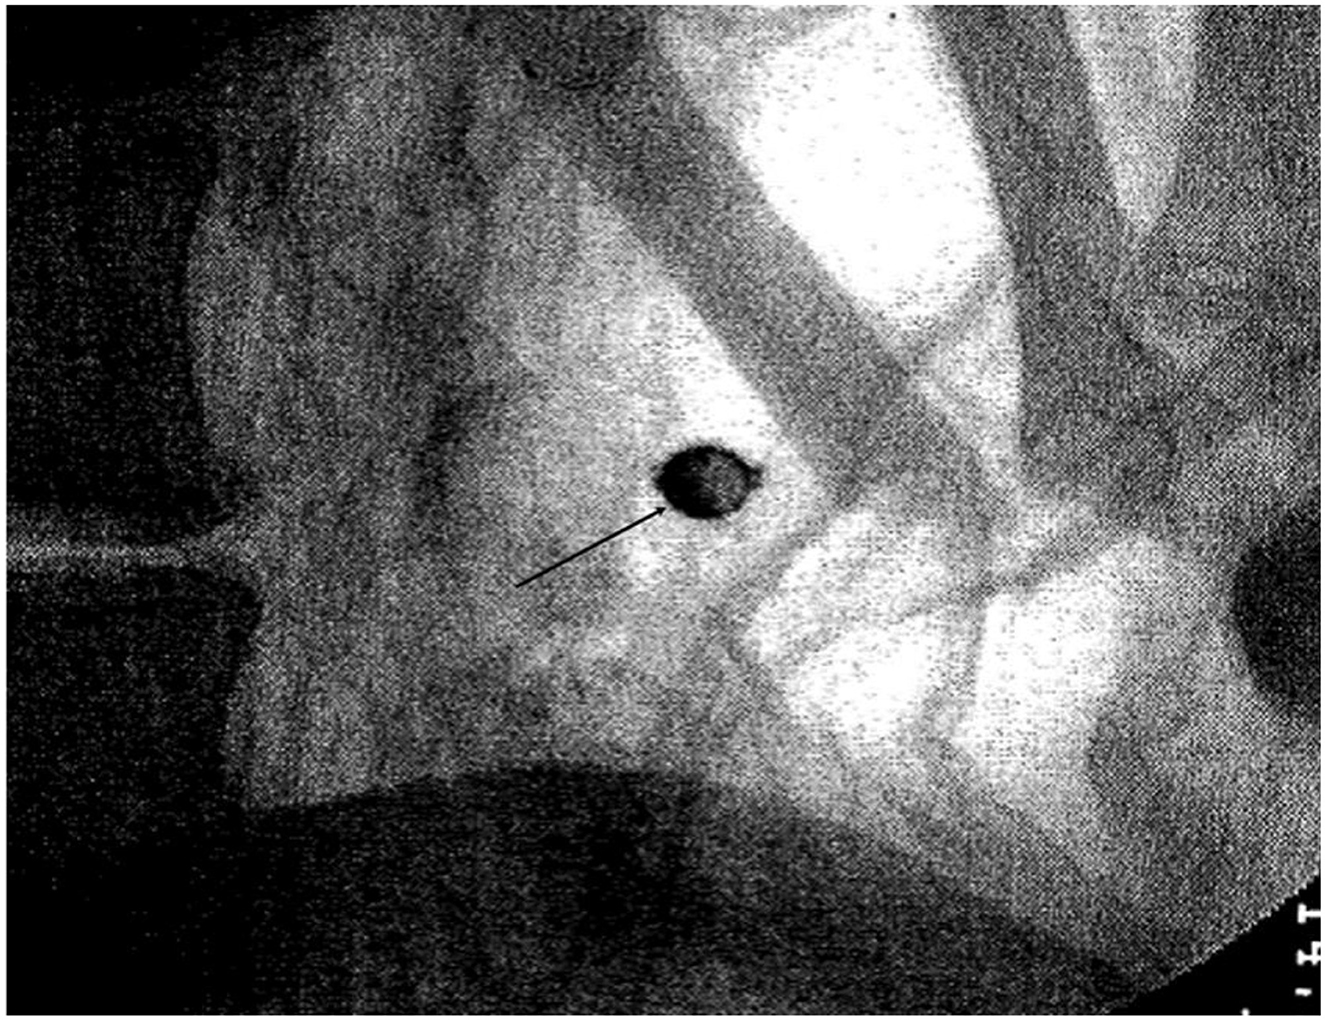

Αιώνες αργότερα, ένα αντικείμενο σε σχήμα κάψουλας που εντοπίστηκε σε ακτινογραφία της μούμιας αποκάλυψε ότι ο κληρικός είναι πιθανό να είχε ένα πιο σκοτεινό θάνατο, υποδηλώνοντας δηλητηρίαση.

Μέχρι σήμερα, ένα γυάλινο αντικείμενο σε σφαιρικό σχήμα που είχε εντοπίσει σάρωση μέσω ακτίνων Χ, το 2000, είχε οδηγήσει τους επιστήμονες στο σενάριο της εκούσιας δηλητηρίασης.

Ωστόσο, σύμφωνα με τον Νέρλιχ και τους συνεργάτες του, το σφαιρίδιο που στις δύο άκρες του έφερε μικρές τρύπες, ίσως ήταν μέρος ενός κομποσκοινιού που είχε μπερδευτεί στο υλικό ταρίχευσης.